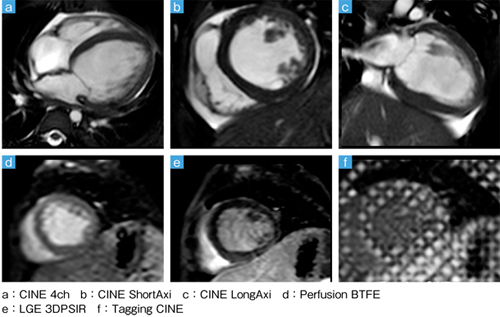

■症例3:フォンタン手術術後(18歳,女性)の心臓MRA

■症例5:心筋症(1歳,男児)のシネMRI